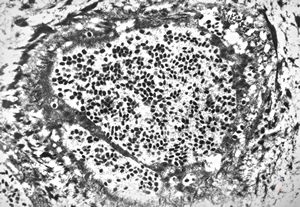

F, 1m. | sepsis - mycotic dermal lesions

M, 57y. | dermal mycotic lesion

M, 57y. | dermal mycotic lesion … toluidine-blue stained semithin section

M, 28y. | leishmaniosis … skin of the cheek

M, 28y. | leishmaniosis … skin of the cheek